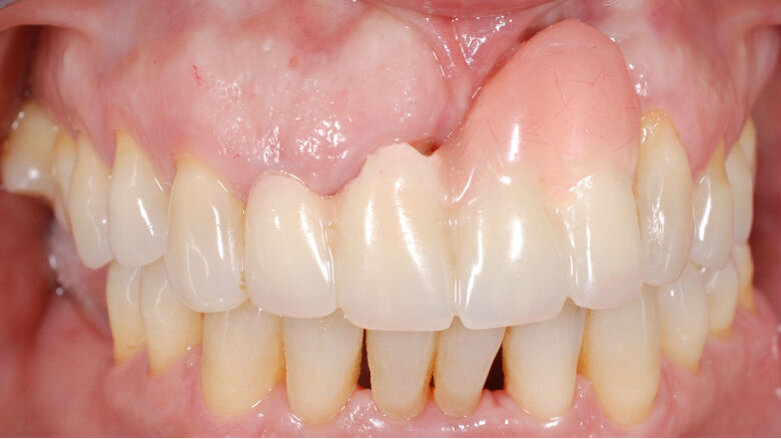

In questo articolo presentiamo un caso clinico che dimostra come il posizionamento improprio di un impianto può rendere impossibile la riabilitazione protesica, che richiede una nuova pianificazione chirurgica e riabilitativa per ottenere l’estetica desiderata. La paziente si presenta alla nostra osservazione con una riabilitazione protesica incongrua, con flangia in resina, a supporto dentale ed implantare, con la presenza di un impianto in posizione 2.1 vestibolarizzato e con l’emergenza nel fornice, in mucosa alveolare. Dalla valutazione della Tac si evince la posizione errata dell’impianto e la perdita consistente in senso trasversale della compagine ossea (Figg. 1, 2). Pertanto si opta per il seguente piano di trattamento che prevede: rimozione dell’impianto e preparazione protesica dell’elemento 2.3, confezionamento di un primo provvisorio a supporto dentale che servirà a guidare la guarigione dei tessuti (Figg. 3-7). A distanza di 4 mesi si procede a un innesto epitelio connettivale libero con prelievo dal palato per compensare il gap dei tessuti molli in senso trasversale, quindi viene ribasato il provvisorio in modo tale da favorire la guarigione dei tessuti (Figg. 8-11). A 9 mesi dalla maturazione dei tessuti si procede alla finalizzazione protesica fissa a supporto dentale (Figg. 12-14).

Fig. 12 - Guarigione a 9 mesi.

Fig. 13 - Visione occlusale che evidenzia l’incremento dello spessore dei tessuti molli.

Fig. 14 - Finalizzazione protesica.

Indipendentemente dalla causa, quando un impianto non è ben posizionato, la riabilitazione protesica potrebbe non essere adeguata dal punto di vista meccanico, funzionale ed estetico. Nel caso qui presentato, era necessaria la rimozione dell’impianto e una nuova pianificazione chirurgica e protesica. Nonostante i limiti estetici della riabilitazione protesica iniziale, considerando che non è stato eseguito alcun innesto di tessuto osseo, senza reinserire l’impianto, ma gestendo adeguatamente i tessuti molli si è riusciti ad ottenere un risultato estetico valido e predicibile nel tempo.